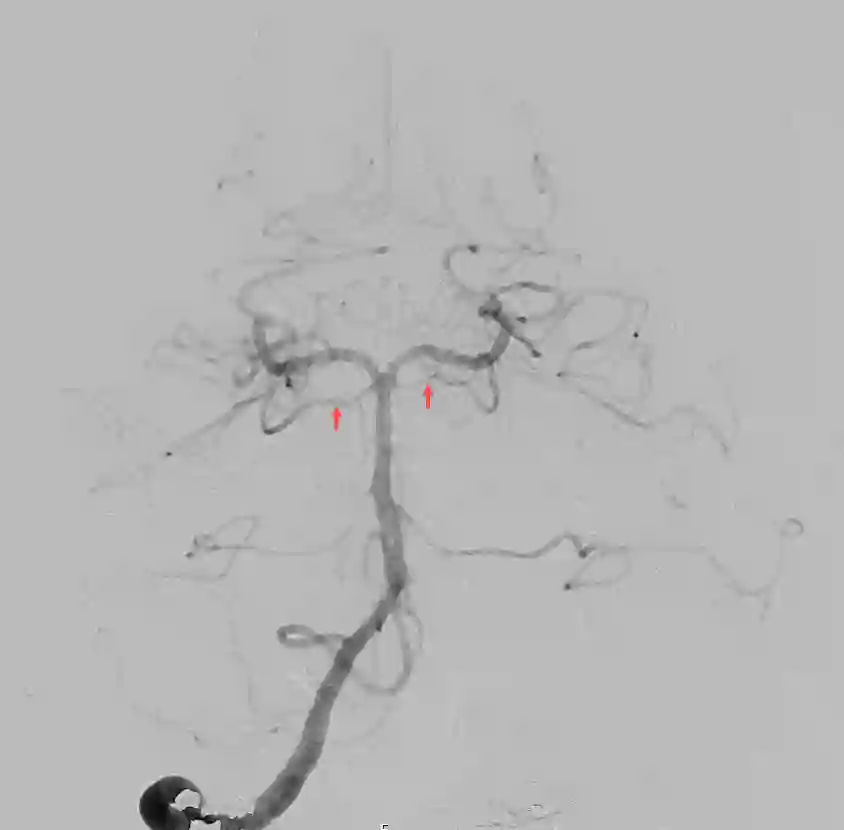

Abbildung

Bildgebung

Der Goldstandard zur optimalen Darstellung der Arteria cerebelli superior ist die digitale Subtraktionsangiographie.